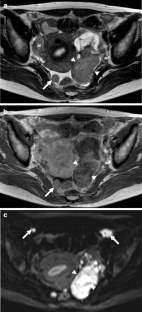

Fig. 7a–d